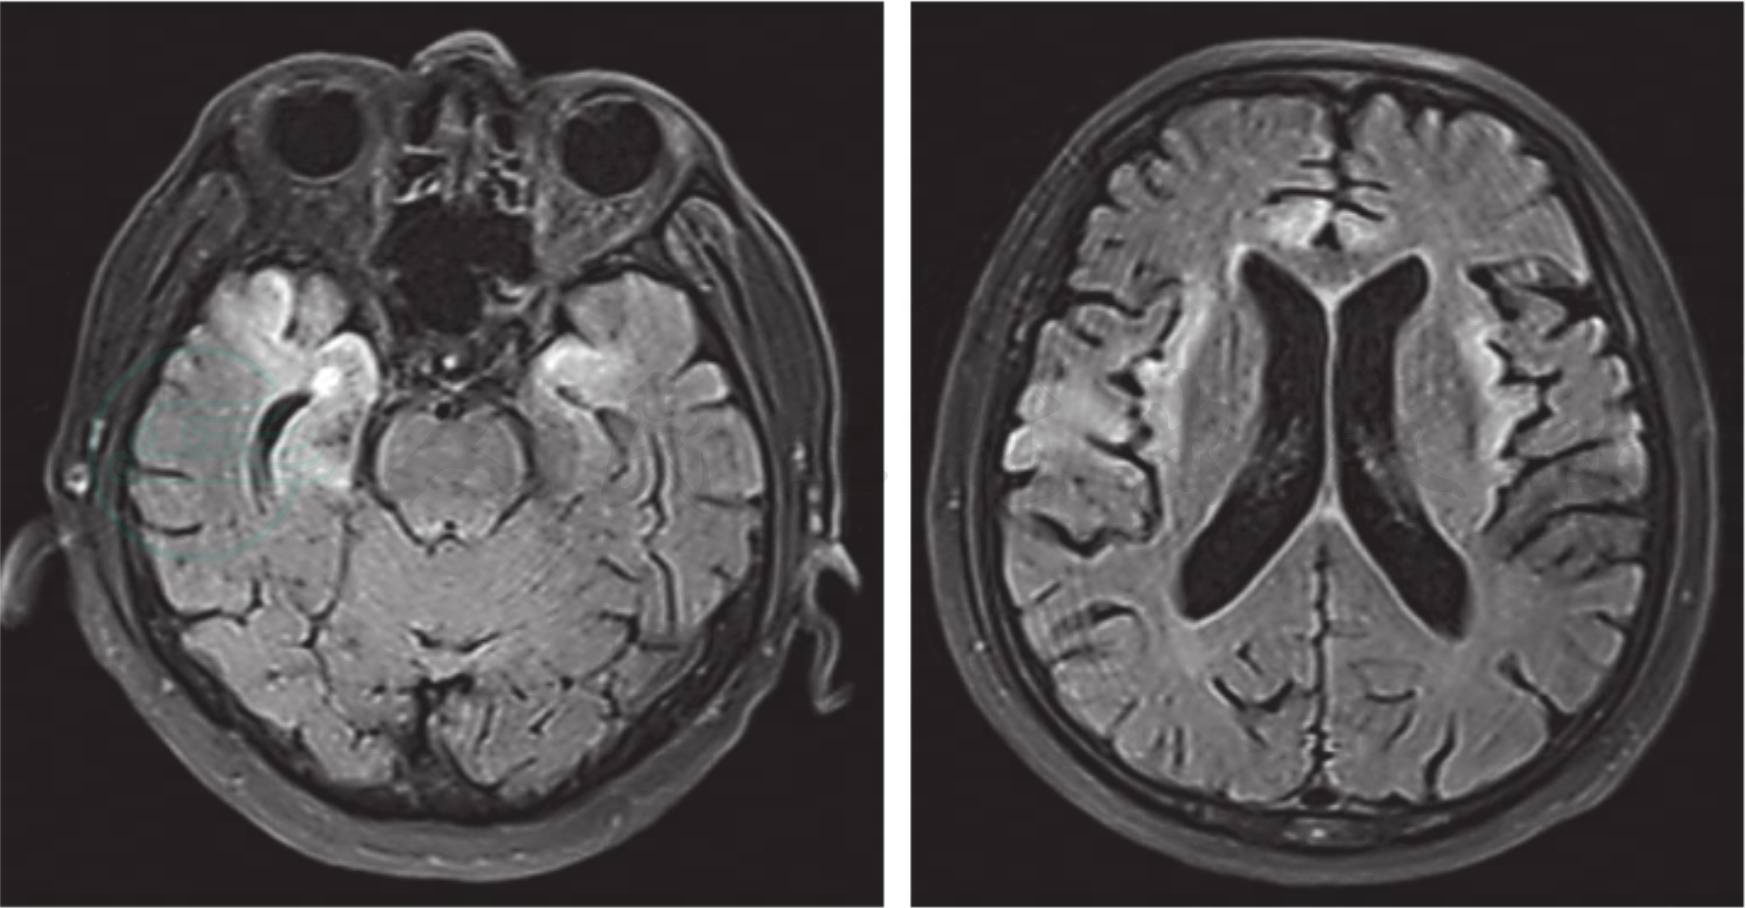

头部MRI显示以皮层为主的脑实质病变(图1)。

图1 单纯疱疹病毒1型脑炎

头部MRI显示双侧额叶、颞叶、岛叶皮层异常信号。